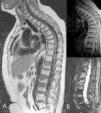

La vía de abordaje transpedicular puede ser a través de los 2 pedículos o laterotranspedicular a través de un solo pedículo (fig. 2).

Figura 2. A: acceso transpedicular; es la vía de abordaje requerida para la realización de la cifoplastia (2 accesos). B: acceso laterotranspedicular; con un trayecto oblicuo es posible acceder a la región central del cuerpo vertebral, con esta técnica se evita una punción al paciente y se acorta el tiempo del procedimiento.

Para poder realizar el acceso laterotranspedicular es necesario que la trayectoria de la aguja, para ello se inclina el haz de rayos X hasta que la apófisis espinosa se superponga con el pedículo contralateral y el pedículo a puncionar se identifique correctamente (fig. 3).

Figura 3. A: reconstrucción con TC coronal de los cuerpos vertebrales de 2 vérterbras tratadas. B: posición oblicua para el acceso laterotranspedicular, control de la aguja perpendicular. C: control con TC de la distribución del cemento en el cuerpo vertebral. D: radiografía lateral, sea oblicua; control de vertebroplastia, 3 niveles.